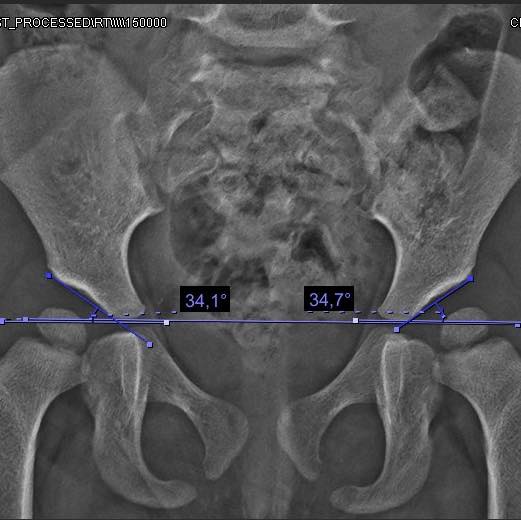

Ayer tuvimos la enorme alegría de dar de alta a Valentina, una pequeña de 3 años. Llegó a consulta y le detectamos una displasia de cadera que, lamentablemente, no se identificó a tiempo por la falta del tamiz de cadera. Le realizamos la cirugía para corregir la displasia y hoy sus caderas están dentro de parámetros normales. Con este tratamiento, logramos prevenir un desgaste prematuro y reducir la necesidad de una prótesis en el futuro. ¡Gracias, Valentina, por los panes de muerto que nos trajiste!